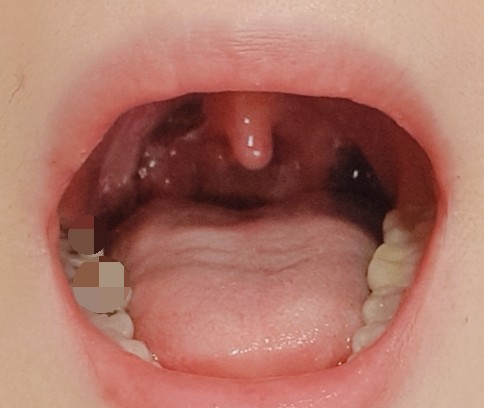

수술은 마취제 덕분에 전혀 아프지 않지만 너무 무서웠어요. 오랜 시간 호흡을 천천히 하면서 참았고 마침내 수술을 마치고 화면에 수술한 부위를 보여주었어요. 생각보다 수술 부위가 넓다고 하셔서 염증(편도결석) 주머니를 다 제거했다고 합니다.

검은색 부분이 편도선 제거 수술